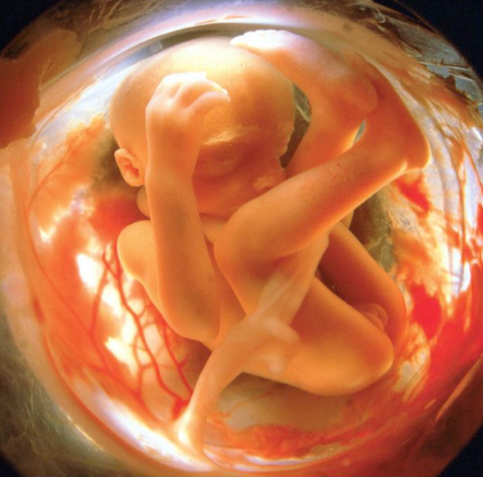

Al final de la etapa embrionaria tenemos un ser de 3cm y un peso de 30gr que ya tiene forma humana y un sistema nervioso capaz de reacciones rudimentarias.

-Crecimiento muy rápido, pero con considerable variación entre fetos.

-Desarrollo de los músculos y formación de los huesos.

-Los órganos principales completan su formación aunque no son funcionales.

-Funcionamiento de los órganos del cuerpo (aparato cardiovascular, digestivo y excretor).

-Formación del pelo, cejas, pestañas, uñas y brotes de los dientes.

-Desarrollo encefálico: Los órganos sensoriales comienzan a responder a estímulos. Desarrollo de muchas neuronas nuevas (neurogénesis) y sinapsis entre neuronas (sinaptogénesis).

-Aparición de patrones de ondas encefálicas que parecen corresponderse al ciclo sueño-vigilia.